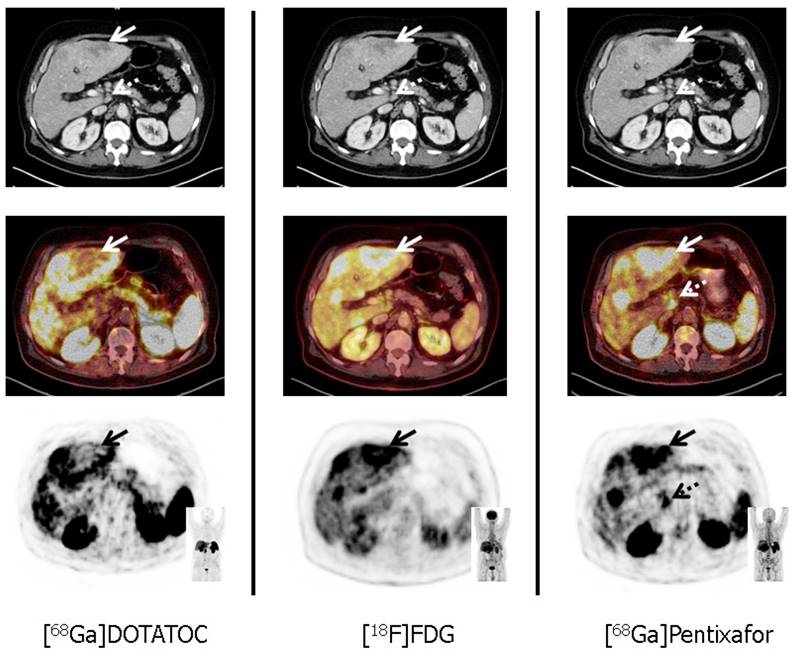

Figure 2

Tumor heterogeneity in a patient with a G3 gastric neuroendocrine tumor (NET) and liver metastases (patient #11; Ki67: 90%). In accordance with G3 NET, hypermetabolic hepatic metastases demonstrate loss of somatostatin receptor (SSTR) and up-regulation of CXCR4 expression (solid arrows, corresponding SUVmax: 10.3 for [68Ga]Pentixafor, and 3.8 for [68Ga]DOTATOC, respectively). Moreover, [68Ga]Pentixafor provides additional information on disease extent by exclusively detecting a coeliacal lymph node suspicious for metastatic disease (dotted arrows). All transaxial PET/(CT) images are displayed identically with a window level between 0 and 5.5. [68Ga]DOTATOC = 68Ga-DOTA-D-Phe-Tyr3-octreotide, [18F]FDG = 18F-fluorodeoxy-glucose.